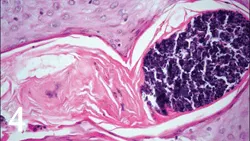

4. Early dermatohistopathologic lesions involve lymphoplasmacytic periductal inflammation, sebaceous gland duct dilation, and follicular keratosis with plugging and dilation (Figure 3). More advanced lesions show evidence of folliculitis (Figure 4), furunculosis, pyogranulomatous sebaceous adenitis, and dermatitis. Staphylococcus spp organisms and Malassezia spp may be present in comedones and surface crusts.

Figure 4. Histopathology of a comedone specimen showing suppurative inflammation and intrafollicular coccoid bacteria (magnification, 400×)